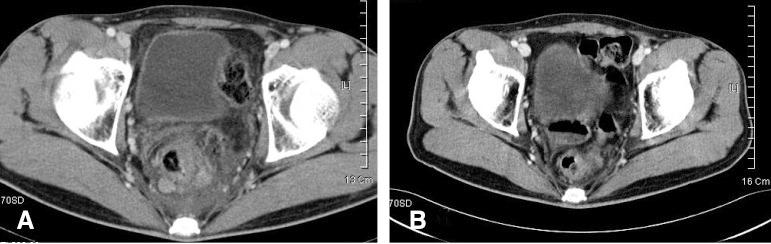

Anorectum is a rare location for malignant lymphoma. Involvement of is rare even for the lynphoma associated with acquired immune deficiency syndrome (AIDS), and AIDS has a relatively increased frequency of anorectal lymphoma. Most lymphomas in AIDS patients are of a B-cell origin, and T-cell lymphoma of the gastrointestinal tract is extremely rare. We report here on a case of anorectal and gastric peripheral T-cell lymphoma, unspecified (PTCLu) in a non-AIDS patient. A previously healthy 29-year-old man presented with hematochezia and tenesmus that he had suffered with for the previous 2 months. Sigmoidoscopy showed anal and rectal submucosal tumor. Multiple round-shaped, flat and elevated lesions were noted on the gastric antrum and body as well. He underwent excisional biopsy for the anal mass and the diagnosis was PTCLu. Biopsies of the gastric lesions gave the same diagnosis. There was no lymphoma involved in the bone marrow. At admission, no antibodies against human immunodeficiency virus were detected. He underwent systemic chemotherapy and upfront autologous stem cell transplantation.

https://cdn.ncbi.nlm.nih.gov/pmc/blobs/bff0/3891034/12bfaa77ccbd/kjim-21-262-g001.jpg